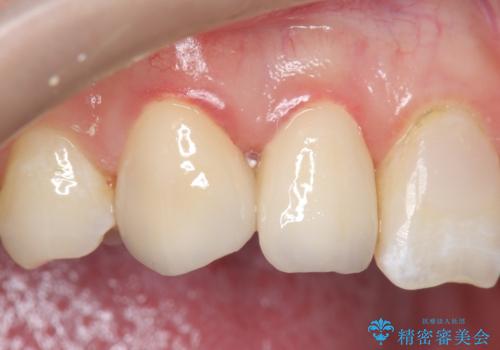

- 右上2、3番目の歯の色・形が気になるといらっしゃった方の症例です。

古い樹脂を除去後、オールセラミッククラウンによる補綴を行いました。